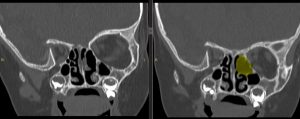

CT-ul efectuat imediat postoperator a confirmat ablația macroscopic completă (fig 2)

Figura 2: imagini CT comparative preop-postop la finalul interventiei chirurgicale